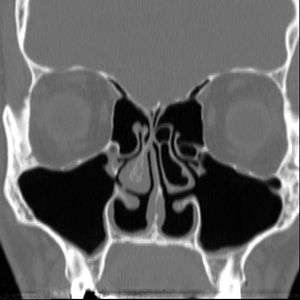

| Altered nasal anatomy after bilateral subtotal inferior turbinectomy | |

Empty nose syndrome (ENS) is a rare clinical syndrome in which people who have clear nasal passages experience a range of symptoms, most commonly feelings of nasal obstruction, nasal dryness and crusting, and a sensation of being unable to breathe.[1] People who experience ENS have usually undergone a turbinectomy (removal or reduction of turbinates, structures inside the nose) or other surgical procedures that interfere with turbinates; the overall incidence is unknown but it appears to occur in a small percentage of those who undergo nasosinal procedures.[1][2] It appears to be a health care caused condition but its existence as a medical condition, cause, diagnosis and management are controversial.[1] No one disputes that people with the symptoms suffer a great deal.[1][2][3]

There are no objective physical examination findings that definitely diagnose ENS.[1] Generally, one or more turbinates may be reduced or absent when viewed in medical imaging or via endoscope with no sign of physical obstruction, the mucosa will be dry and pale, and there may be signs of secondary infection.[1]